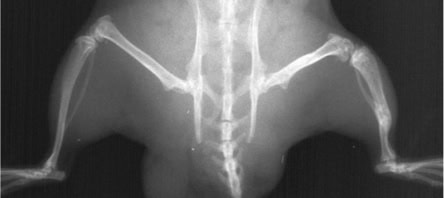

Researchers at Armbruster have succeeded in producing polyclonal anti-tumor-BSP antibodies in chickens, which resulted in the destruction of cancer cells in vitro as well as in animal models (see Fig. 1). Since chicken antibodies are not suitable for use in therapy for human patients, recombinant antibodies were identified that were produced from the HuCAL antibody collection Antibodies by Design. This technology provides a method to identify antibodies whose structure corresponds to human antibodies, which are therefore tolerated by the immune system.

X-rays of a nude rat show bone tumour after injection of tumour cells: After an average of 28 days, lytic metastases could be detected by X-rays; on day 35, the treatment with an anti-tumour-BSP antibody was started. Until day 60, the tumour resulted into a size of up to 40 mm2. Afterwards, the healing started and the tumour decreased its expansion to 25 mm2 (Day103).